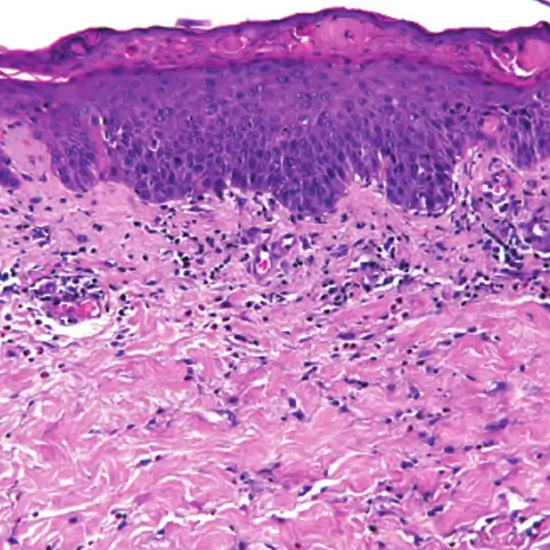

Histopathology skin biopsy is a procedure that removes a small sample of skin for testing under a microscope. This test is performed to diagnose/ detect skin cancer, skin infections, and skin disorders such as psoriasis and eczema. This is also known as skin cancer biopsy, basal cell biopsy, squamous cell biopsy, or melanoma biopsy.

The doctor recommends a skin biopsy to diagnose/ detect the skin disorders such as psoriasis and eczema, bacterial or fungal infections of the skin, and Skin cancer at its early stage. If the patient is experiencing certain skin symptoms such as persistent rash, scaly or rough skin, Open sores, mole, or abnormal growth